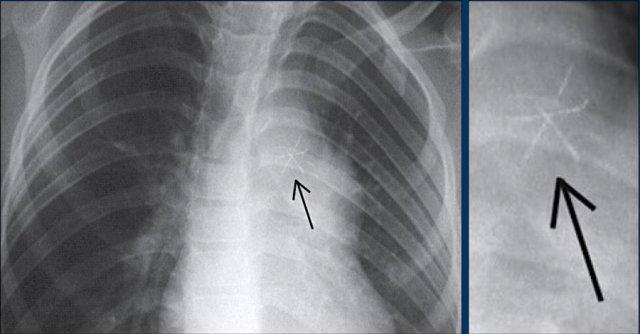

Hình ảnh được chụp ngay sau khi đặt ICD.

Có hình ảnh tràn khí màng phổi nhỏ (mũi tên).

Đây là biến chứng thường gặp nhất.